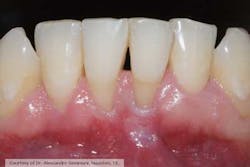

Fig. 1: Initial situation, before free gingival graft. Note the lack of gingiva buccal to teeth Nos. 24 and 25.

Fig. 2: Follow-up at eight weeks. The free gingival graft was successful in increasing the amount of gingival adjacent to teeth Nos. 24 and 25.